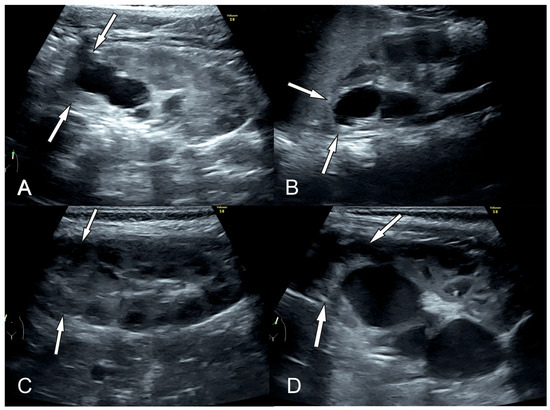

3.1. Ultrasound